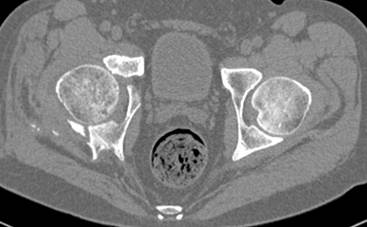

высылаю дополнительно сканы.

итак, второй вариант: высокий двухколонный с вовлечением КПС... Ни одно из основных повреждений не репонировано, кроме задней стенки. Скорее всего попытка реконструкции вертлуги сейчас будет очень травматичной и не очень эфективной, т.е. вероятный риск более значим, чем ожидаемая польза... Лучше подождать, и потом сразу эндопротез